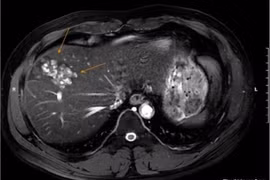

Nam bệnh nhân 41 tuổi ở Hà Nội mới đây được phát hiện tổn thương gan nghiêm trọng do nhiễm sán lá gan lớn vì thói quen ăn đồ sống thường xuyên.